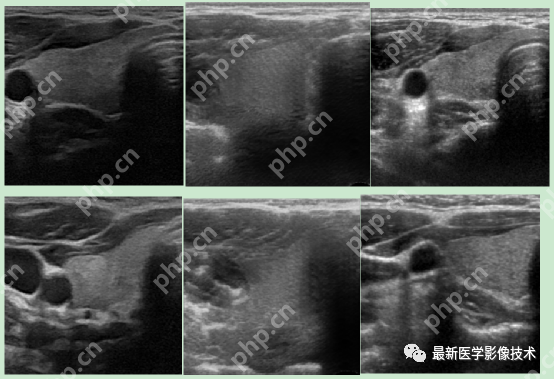

5、验证集部分生成结果

左图为低质量图像,中间为生成的高质量图像,右图为真实的高质量图像。